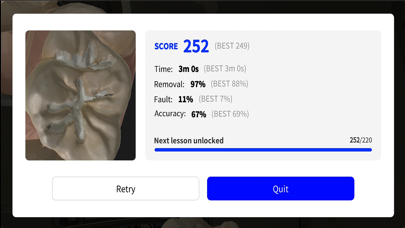

Скриншоты